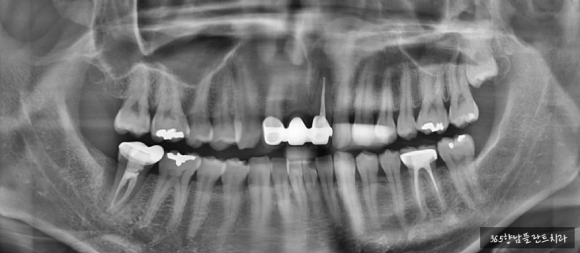

24.03.02 초진 파노라마

환자분께서는 오른쪽 아래 어금니가 붓고 통증이 심해 저희 병원에 방문 해 주셨습니다.

먼저, 엑스레이를 촬영해 치조골 상태를 확인해 보았는데요.

오래전 신경치료와 보철을 씌운 오른쪽 아래(사진상 왼쪽) 어금니 뿌리 주변으로 염증이 심해 치조골이 손상된 상태였습니다.

(빨간색 튜브처럼 표시한 곳이 하치조 신경관)

뿌리 주변으로 고름도 나오고 있고, 하치조 신경.관과 염증이 가까운 위치에 있어 주변 치아에 영향을 주기 전에 빠른 발치가 필요했는데요.